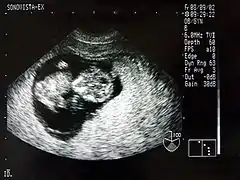

Dans le cadre de la surveillance médicale de la grossesse, une échographie permet d'obtenir une image monochrome d'un fœtus à l'intérieur du ventre de sa mère. Bien que ce soit l'utilisation la plus connue de l'échographie, on utilise également cette technologie pour la détection des troubles d'organes internes (calculs, kystes, cancers).